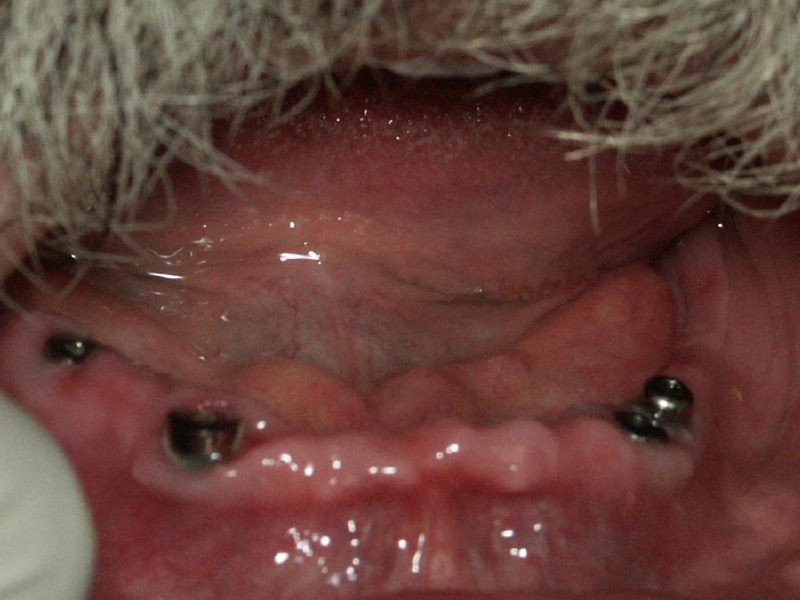

Terminado de Prótesis Hibridas superior e inferior atornillada sobre implantes que van fijas y no se las tiene que quitar el paciente

El mismo paciente en el cual se le colocaron cuatro Implantes inferiores, para elaborarle Prótesis Hibridas que van fijas